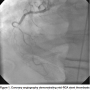

A 6 French JR4 guide was used to engage the RCA. A Prowater wire (Asahi Intecc) was initially advanced but unable to cross the lesion. A PT Graphix wire (Boston Scientific) was then advanced with the use of an Apex 1.5 mm over-the-wire balloon (Boston Scientific) for support to cross the occluded segment into the distal RCA. Due to the degree of thrombus burden, laser atherectomy was performed (Figure 2) using a 0.9 mm ELCA catheter (Spectranetics) with no improvement in flow. Intravascular ultrasound (IVUS) of the entire stented